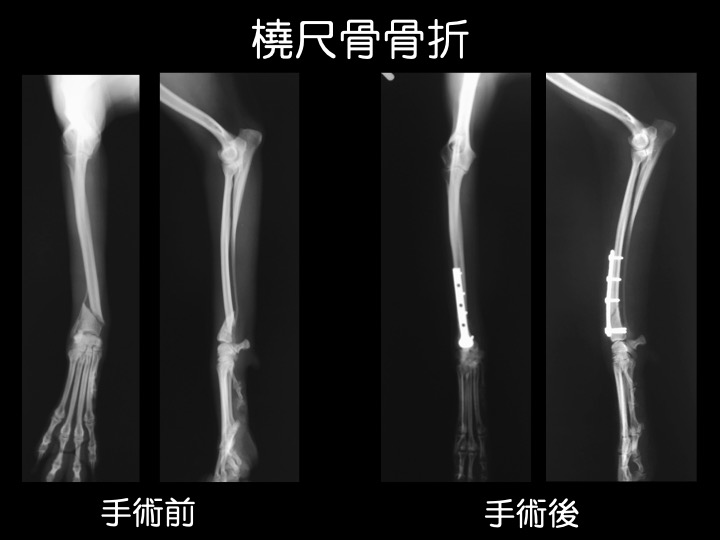

インプラント治療例

・小型犬(トイプードル、ポメラニアンなど)の前腕(橈骨、尺骨)は非常に細く、ソファやベッド、抱っこからの落下が原因で骨折するケースが多く見られます。

・骨折の治療は、ギプス、インプラントなどを用いて行われますが、これらはあくまでも、“骨折が治る=骨がくっつく” ための補助となるものです。

・治療には、適切な運動制限など、ご自宅での管理やケアが大変重要です。

・骨折による骨のズレが大きい場合や、ギプス固定ができない箇所の骨折などが適応になります。

・骨折の部位、動物の大きさや手術用途にあわせて選択できるよう、様々な種類のものが作られています。